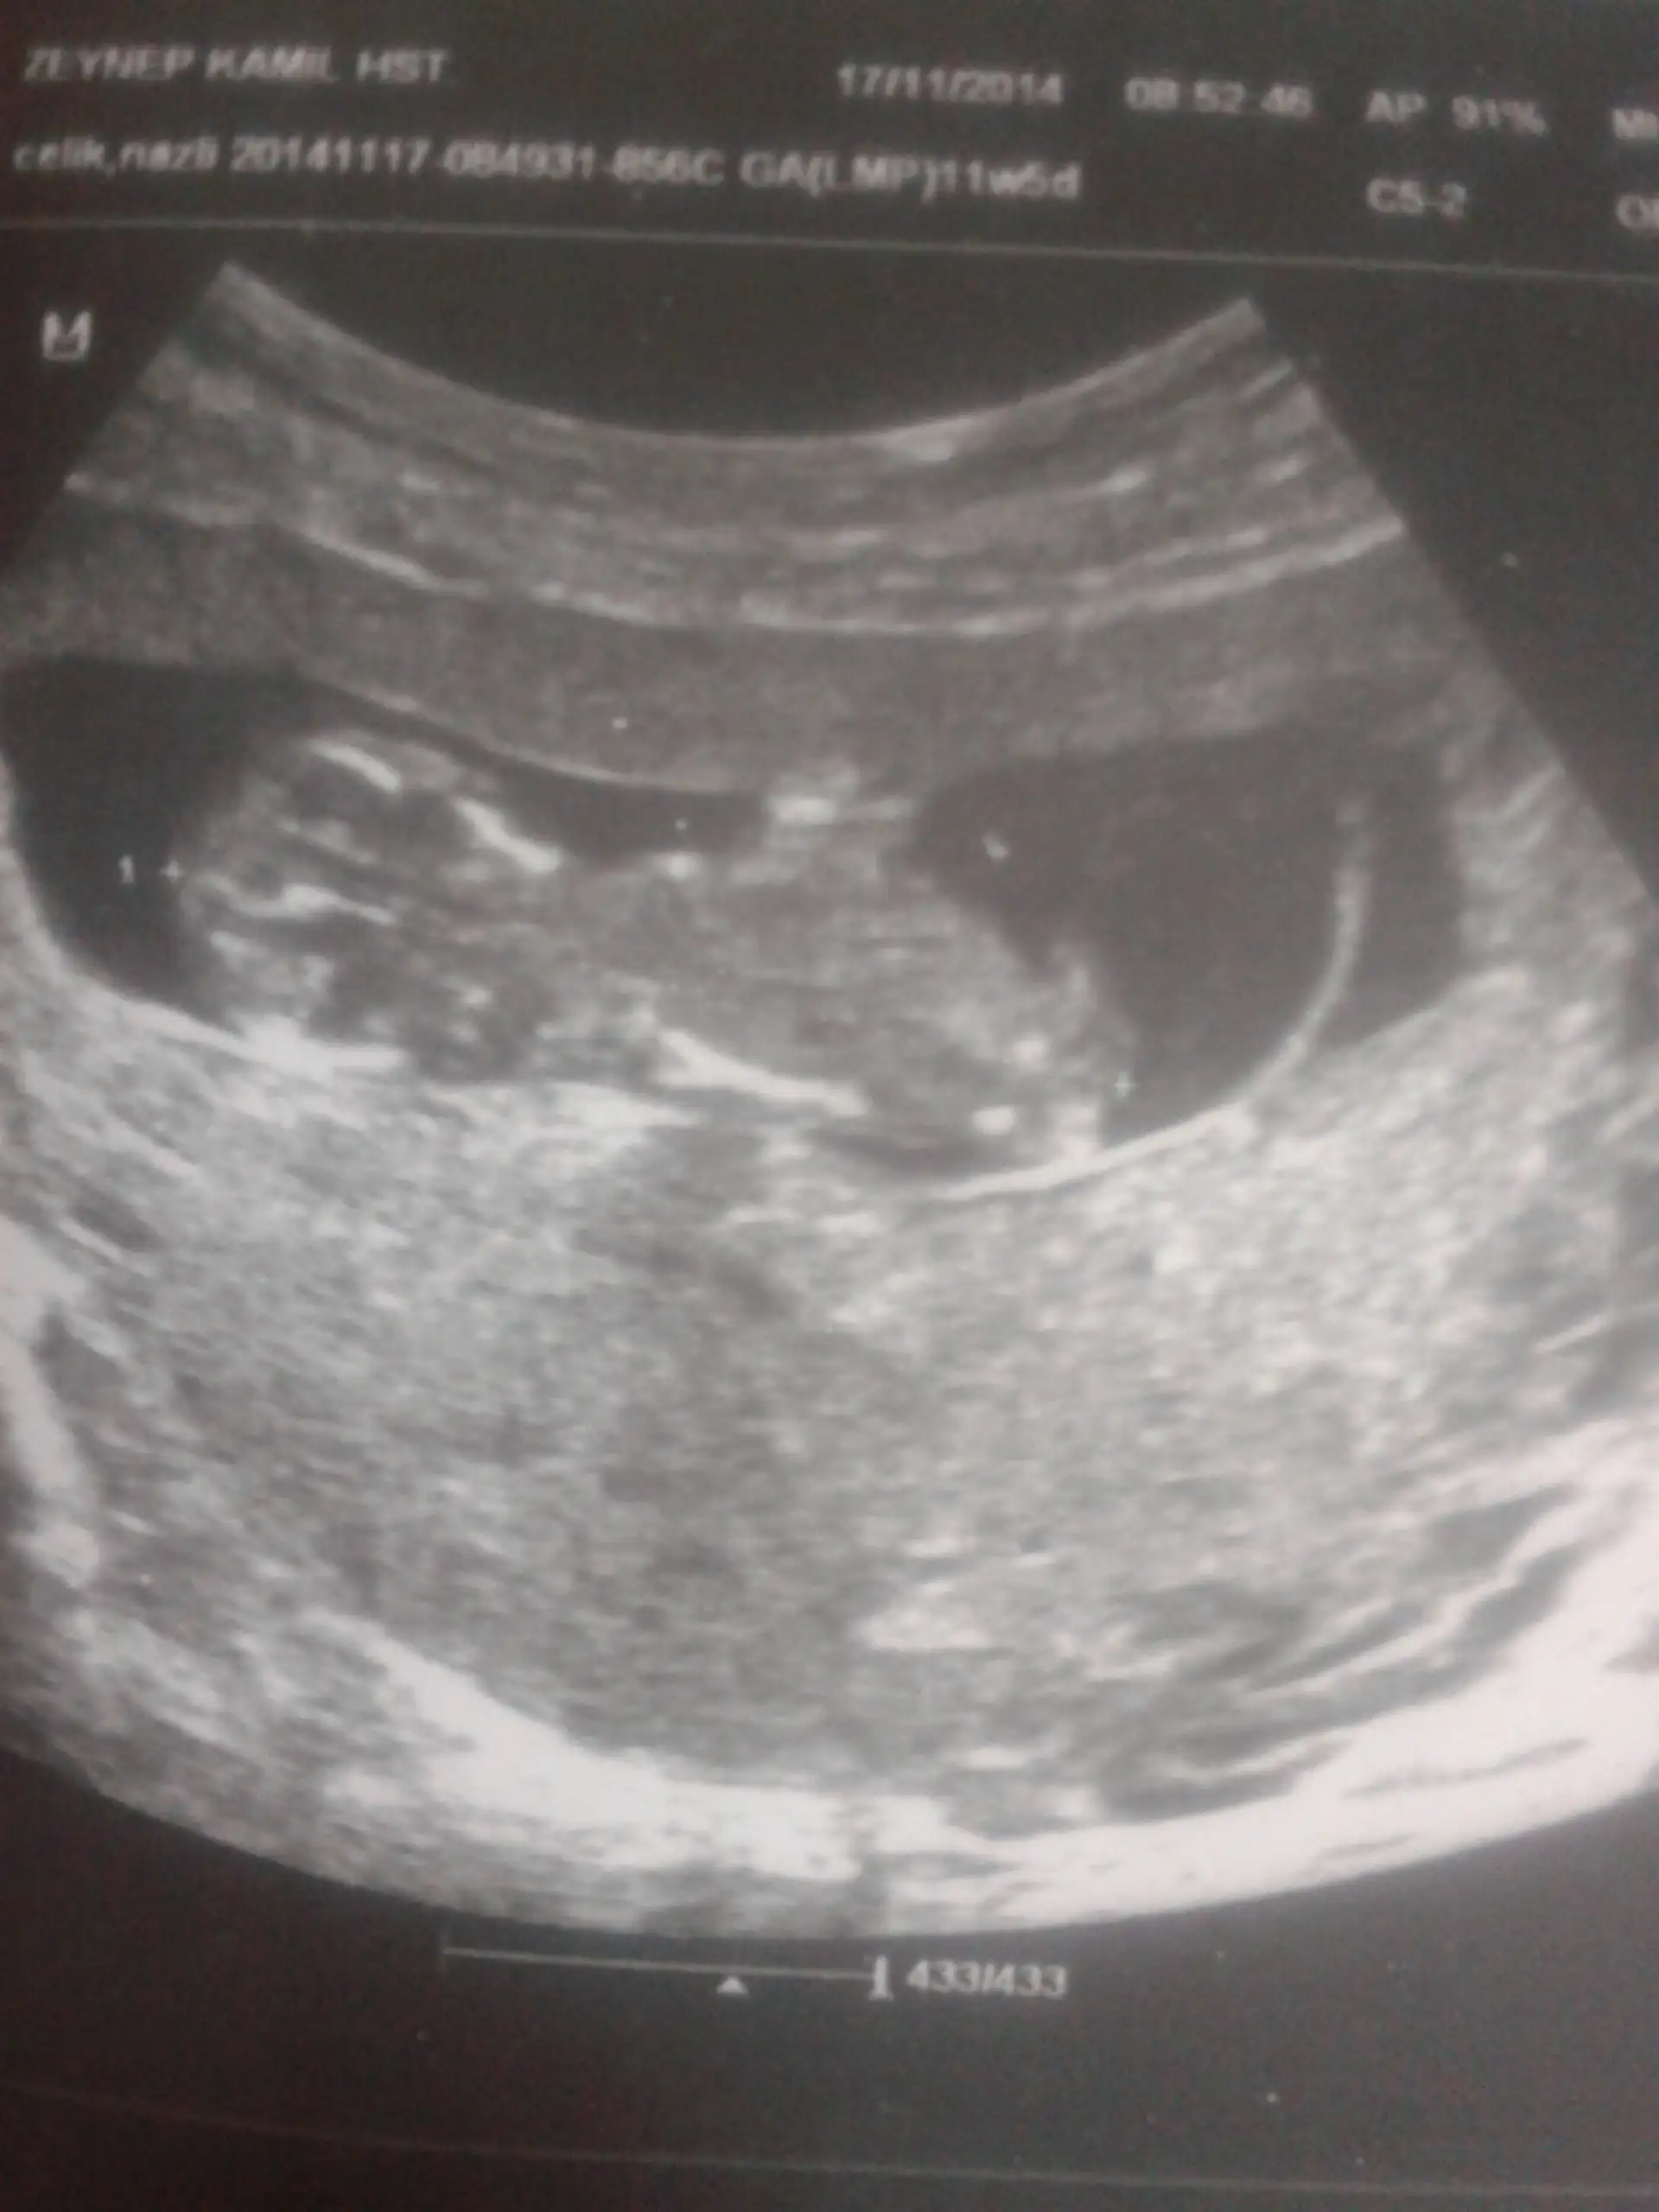

Merhabalar. Benim bebegimede bir baksaniz. Cinsiyetini cok merak ediyorum. Ultrasonda doktor bacaklarinin arasini zoomladiginda iki tane yan yana kucuk toplara benzer birseyler gørdum. Doktora belli oluyor, ama cinsiyeti nedir diye sordugumda bu gordugumuz iki topa benzer cikinti testis olabilir, veya kiz cocogun genital bølgesider olabilir. Birsey søyleyemem dedi. Cok merak ediyorum o iki yuvarlak cikinti ne olabilir acaba ???

Sirti donuk ama uccizgi goruyorum kiz galiba

Canim yanilmiyorsam bir erkek:)

bu haftada nub nerdeyse aynı oluyor cnm en iyi tahmin 12 13 te illa bi yorum yap dersen kız gibi geldi bence iki hafta sabret yeni foto koy